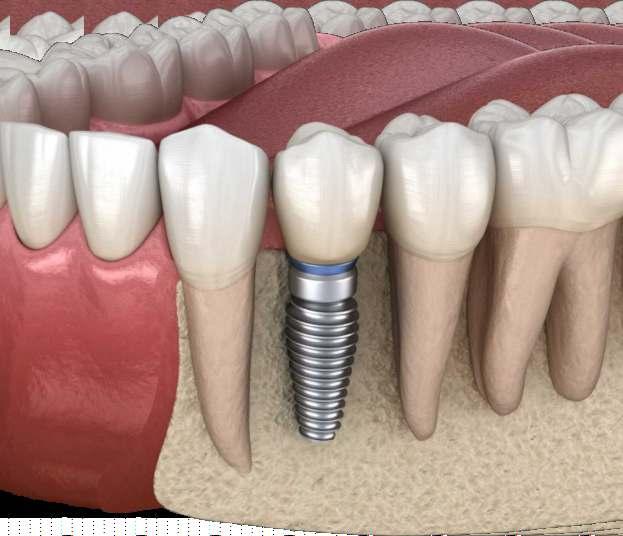

• Implantes dentales